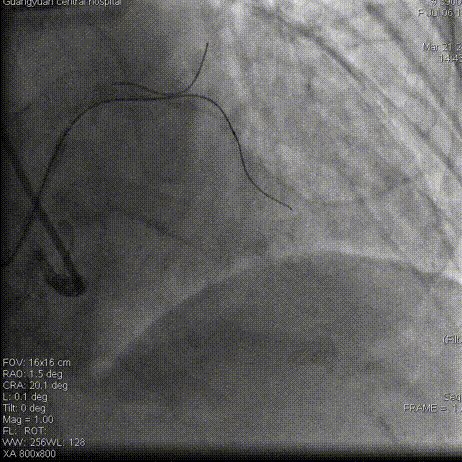

术毕影像

Gaia2通过闭塞段,交换为工作导丝,因左冠前降支扭曲,支架难以通过,在Telescope™ 导引延长导管支持之下顺利释放2枚支架

即刻结果:提高手术安全性,提高手术效率。该款导引延长导管在此次使用过程中未发生器械不良事件。